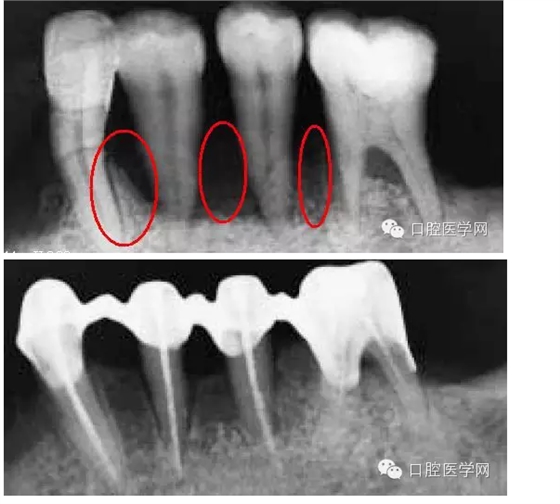

但是,并不是所有的牙齦退縮都是無法在恢復(fù)的。一些患者在去除刺激物包括炎癥,骨是可以基本恢復(fù)原來的健康的(或者說恢復(fù)一些)。當(dāng)然你要通過X-RAY分辨出骨的吸收情況是什么樣。如果象上面第一個(gè)病例那張X-RAY那樣,水平吸收嚴(yán)重就別想了。但如果是下圖這樣,牙齒周圍還保留有骨壁,只要去除炎癥、不良修復(fù)體和調(diào)整咬合情況,骨是可以恢復(fù)的。所以,齦乳頭黑三角最好拍張X-RAY去看看骨的情況,而醫(yī)生不只是對(duì)牙周,同時(shí)對(duì)其他學(xué)科也應(yīng)該有些了解。